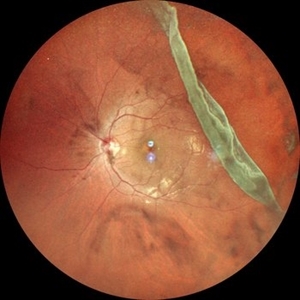

RPE rip in a case of Idiopathic polypoidal choroidopathy RPE rip in a case of Idiopathic polypoidal choroidopathyOct 23 2022 by Anjana Mirajkar, MS Ophthalmology Montage of Fluorescein angiography in a of 61 year old male with RPE rip in a case of Idiopathic Polypoidal Choroidopathy. Photographer: Dr. Anjana Mirajkar -Retina Foundation, Ahmedabad Condition/keywords: Idiopathic polypoidal choroidopathy, RPE rip